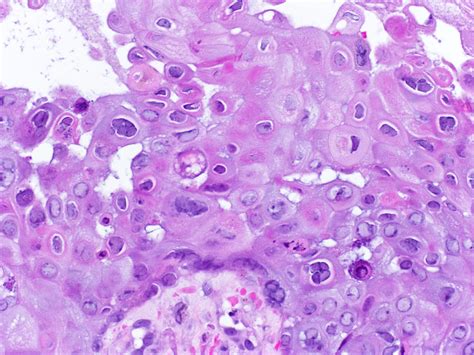

• herpes on breasts pictures